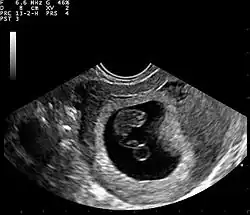

Ultrassom

A Ultrassonografia obstétrica também pode ser usada para detectar e diagnosticar a gravidez. É muito comum um teste de urina domiciliar positivo antes de uma ultrassonografia. Podem ser usadas tanto a abdominal quanto a vaginal, mas a vaginal permite uma visualização mais precoce da gestação. Com a ultrassonografia obstétrica, o saco gestacional (coleção intrauterina de líquido) pode ser visualizado entre 4,5 e 5 semanas de gestação, o saco vitelino entre 5 e 6 semanas e o polo fetal entre 5,5 e 6 semanas. O ultrassom é usado para diagnosticar gestação múltipla, o que não pode ser feito apenas pela presença de hCG na urina ou no sangue.[15] A determinação da idade gestacional do embrião/feto é outro benefício do ultrassom em comparação aos testes de hCG.[16]